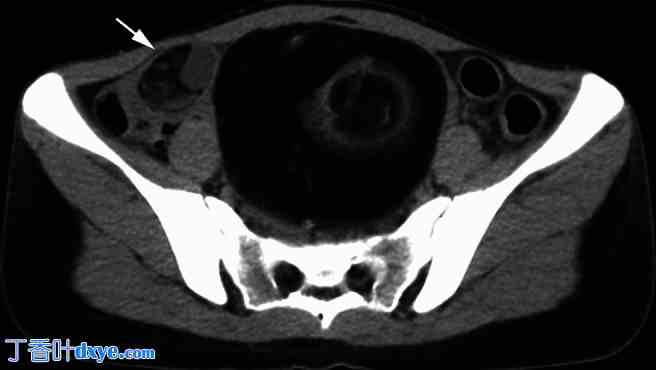

图1

腹腔镜手术前一年的非增强CT扫描。

盆腔中部有一个10厘米长的卵巢畸胎瘤。肿瘤内含有大量脂肪组织和毛球状结构。在同一切片中还观察到另一个3 cm长的畸胎瘤,可能源自右侧卵巢(箭头所示);然而,进行前一个卵巢畸胎瘤切除术的妇科医生并未意识到存在源自对侧卵巢的小畸胎瘤。